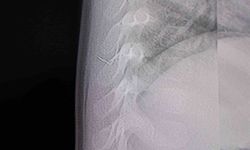

Şanlıurfa’da 16 yaşındaki Bedia Özbay, eşarbını düzeltirken ağzına koyduğu toplu iğneyi yanlışlıkla yuttu. Yapılan tetkiklerde iğnenin sol akciğerine saplandığı tespit edildi. Ailenin çevre illerdeki hastanelere başvurmasına rağmen hiçbir hastane, hastayı kabul etmedi. Bunun üzerine çocuk, Şanlıurfa Mehmet Akif İnan Eğitim ve Araştırma Hastanesi’ne getirildi.

Hastanede görev yapan Çocuk Cerrahisi Uzmanı Op. Dr. Mehmet Emin Balcıoğlu, icapçı olmadığı halde gece saatlerinde hastayı kabul ederek büyük bir özveri örneği sergiledi. Balcıoğlu, bronkoskopi yöntemiyle sol akciğere saplanan toplu iğneyi başarılı bir operasyonla çıkardı. Yaklaşık bir saat süren müdahalenin ardından kız çocuğunun hayati tehlikesi ortadan kalktı. Operasyon sonrası hastanın genel sağlık durumunun iyi olduğu öğrenildi.

Akciğerin sol alt kısmına saplanan toplu iğneyi çıkarttıklarını söyleyen Op. Dr. Mehmet Emin Balcıoğlu, "16 yaşındaki hastamız, öğle saatlerinde başörtüsünü düzeltirken toplu iğneyi yutmuş. Öğleden beri Şanlıurfa Devlet Hastanesi’nde bekliyormuş. Şanlıurfa ve çevre illerdeki hastaneler hastayı kabul etmemiş. Bronkoskopi yöntemiyle sol akciğerin alt kısmına yerleşmiş iğneyi çok şükür başarıyla çıkardık. Hastamızın durumu iyi, birkaç gün misafir ettikten sonra sağlıklı bir şekilde evine göndereceğiz" dedi.